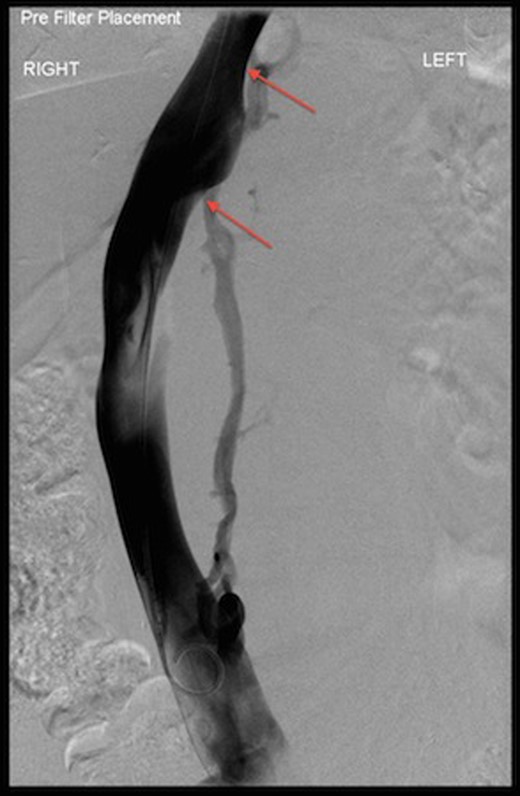

Decision of open repair of AAA was made. After stopping warfarin and reversing its effect, insertion of IVC filter was performed before the surgery. The inferior venogram during this procedure showed that the IVC was displaced to the right with external compression secondary to this large aortic aneurysm (Fig. 5).

Venogram during IVC filter insertion showing indentation by AAA on IVC and its displacement (arrows).